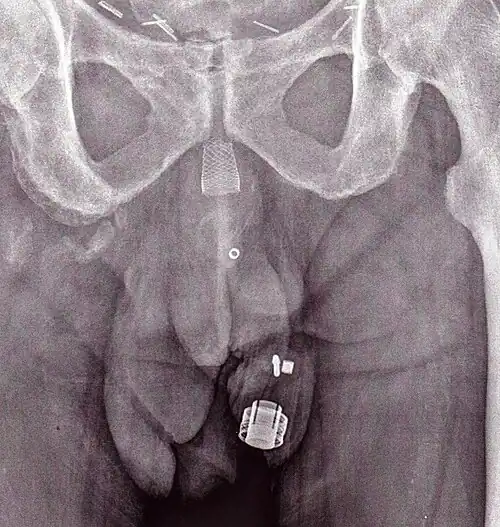

-

Una imagen de rayos X del ZSI 375 implantado. El dispositivo está desactivado: el resorte está comprimido debajo de la parte superior del cilindro. El paciente es incontinente. -